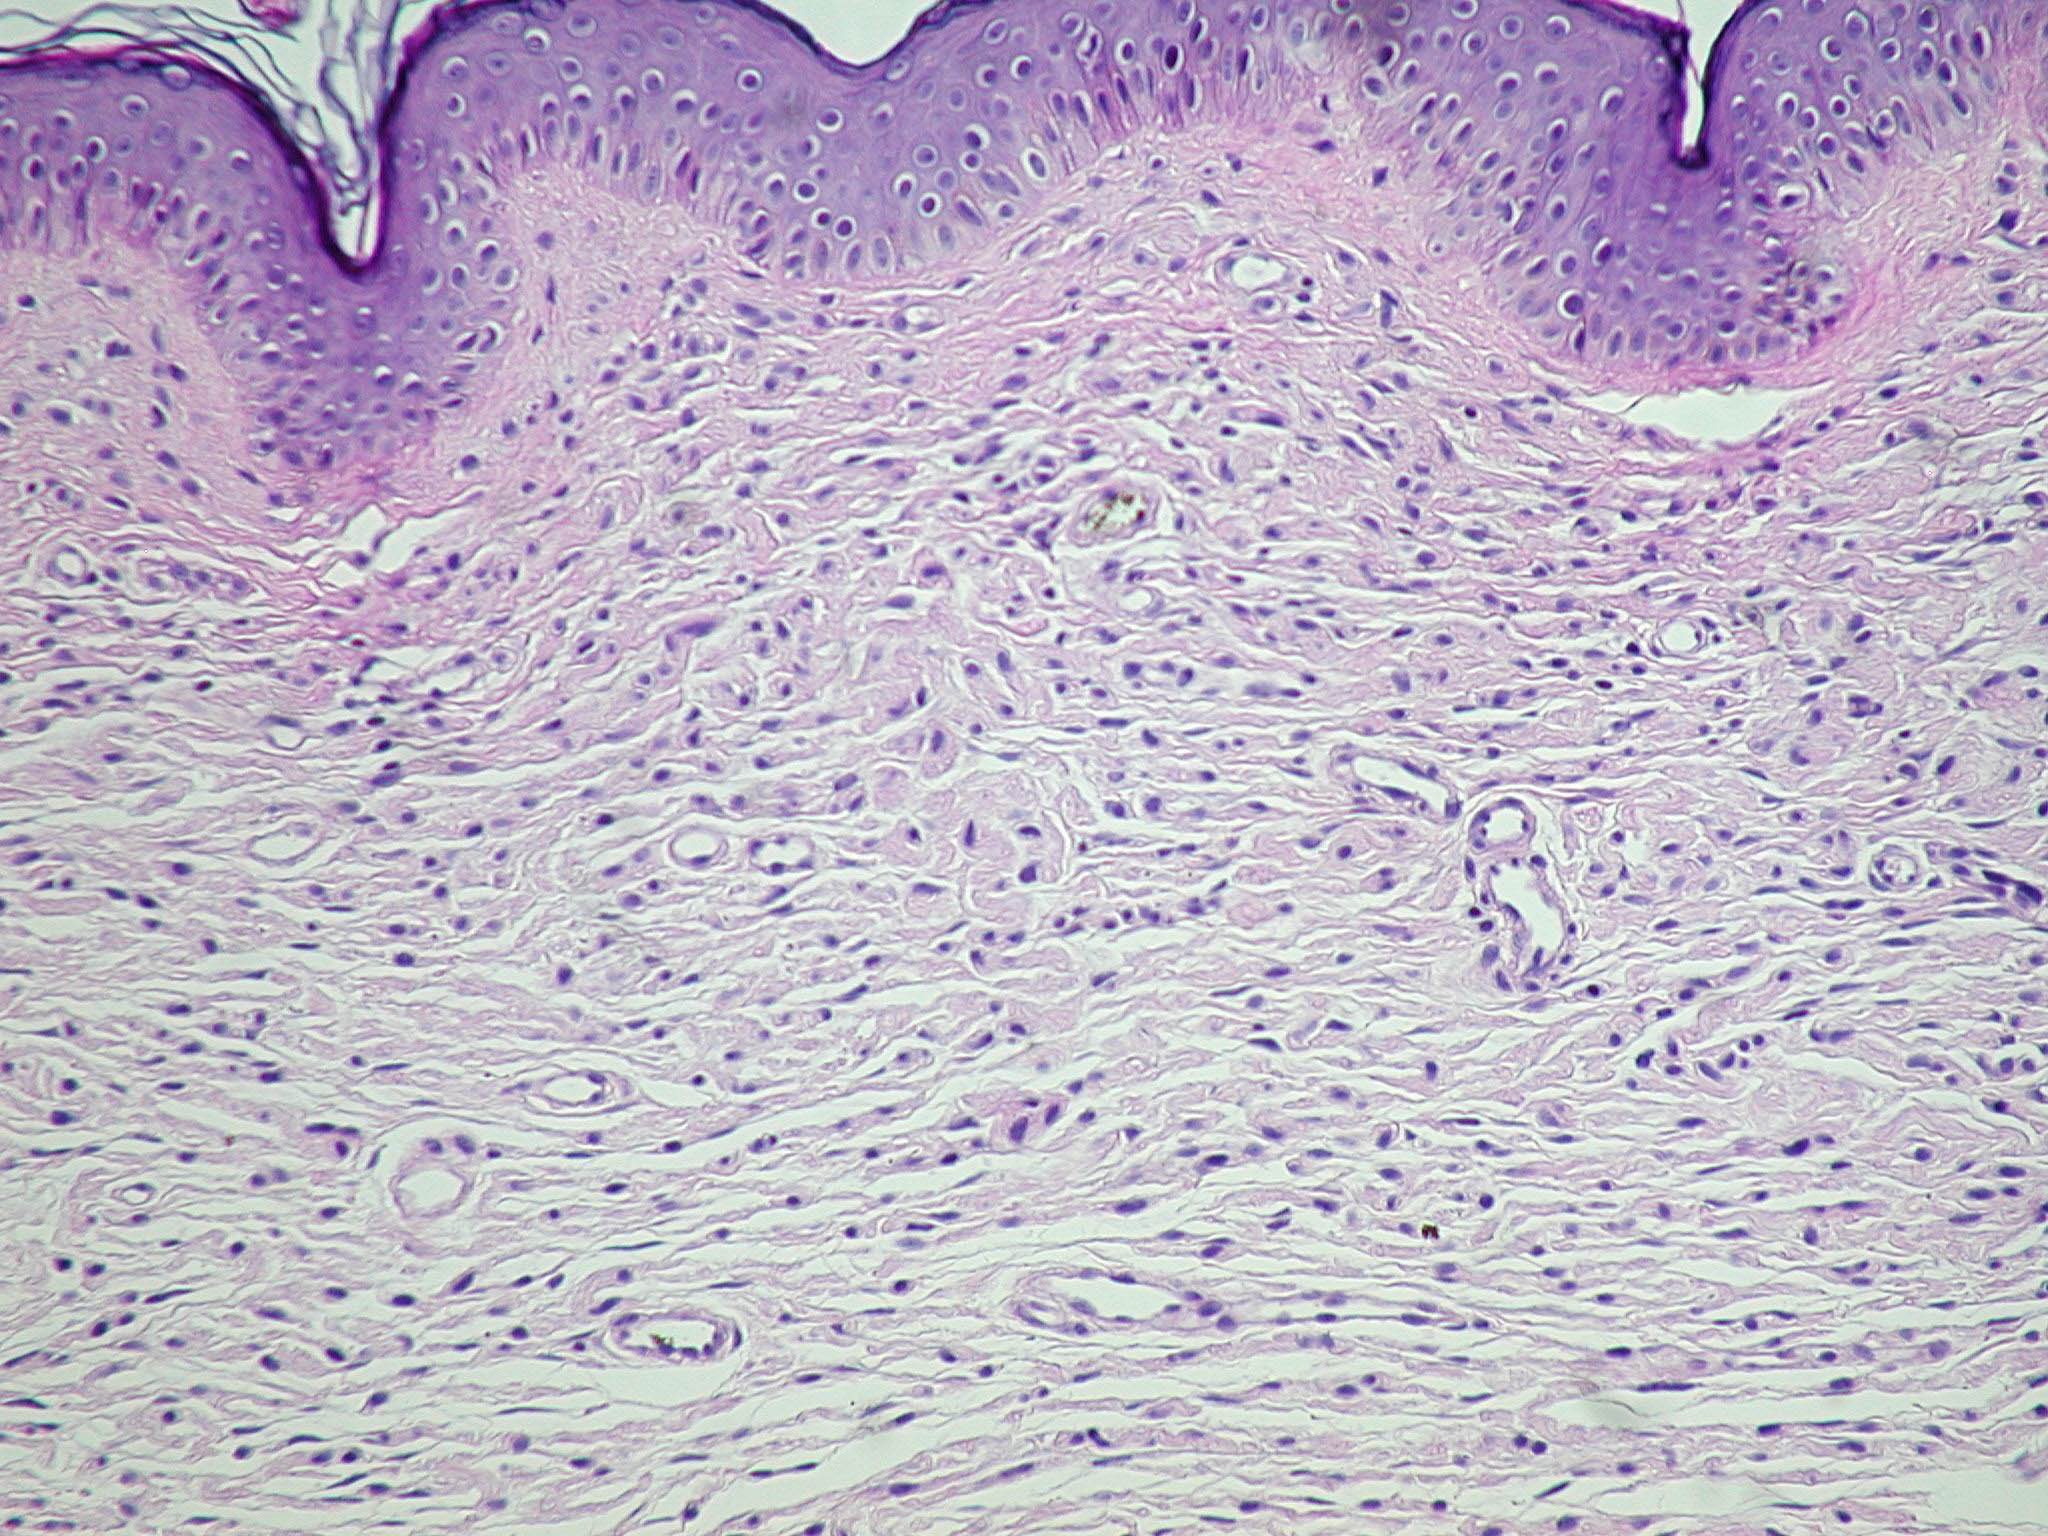

Neurofibroma = الليفوم العصبي